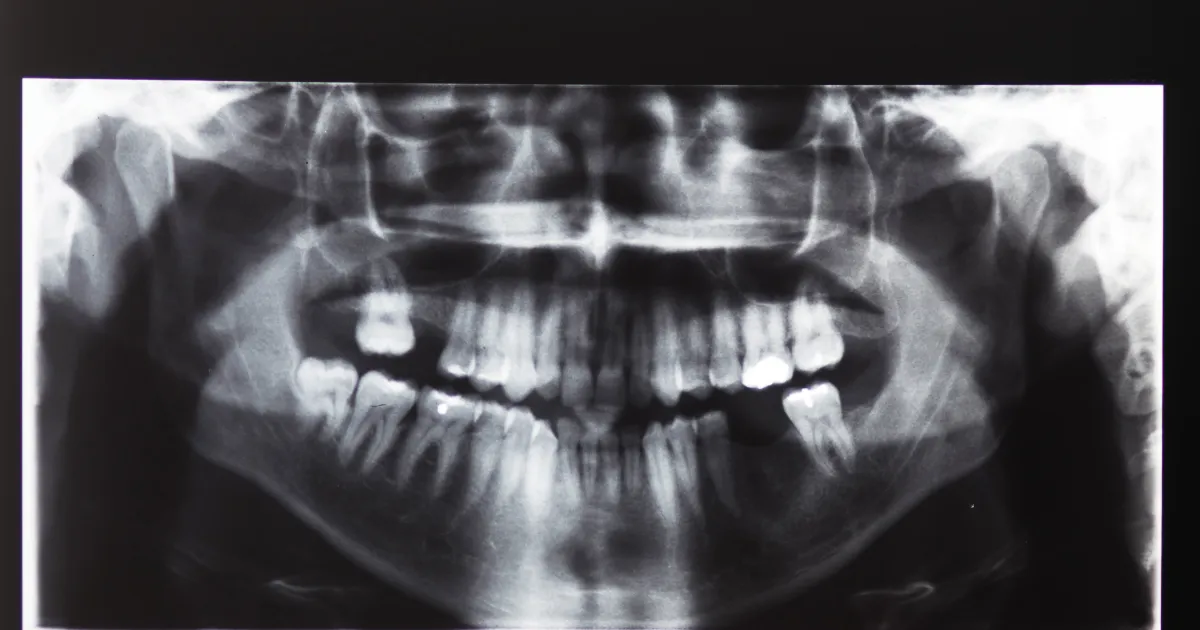

抜歯が必要なとき

歯の状況に応じて抜歯が必要になることがあります。以下は、一般的に抜歯が勧められるケースです。

- 歯の根っこが悪く、治療で改善が見込めないとき

- 歯が割れてしまったとき

- 虫歯の進行がひどいとき

- 悪い影響を与える親知らず

- 矯正や入れ歯の治療において抜いた方がよいとき

歯の根っこが悪く、治療で改善が見込めないとき

根尖性歯周炎など、歯の根の感染が進行し治療で改善が難しい場合には、根管治療をしても治癒が見込めないので感染が広がる前に抜歯を行います。

歯が割れてしまったとき

深い亀裂や割れが発生してしまった歯は、保存治療が難しく、痛みや感染のリスクが高まります。

虫歯の進行がひどいとき

進行した虫歯で歯髄までダメージが及んでいる場合、まずは抜髄といって神経治療ですが、あまりにも痛みがあったり、上記記載のように虫歯があまりにも広がってしまうと抜歯が最良の選択肢になることがあります。

悪い影響を与える親知らず

親知らずが正常に生えておらず、周囲の歯や歯ぐきに悪影響を及ぼす場合、抜歯によって問題の改善が期待できます。